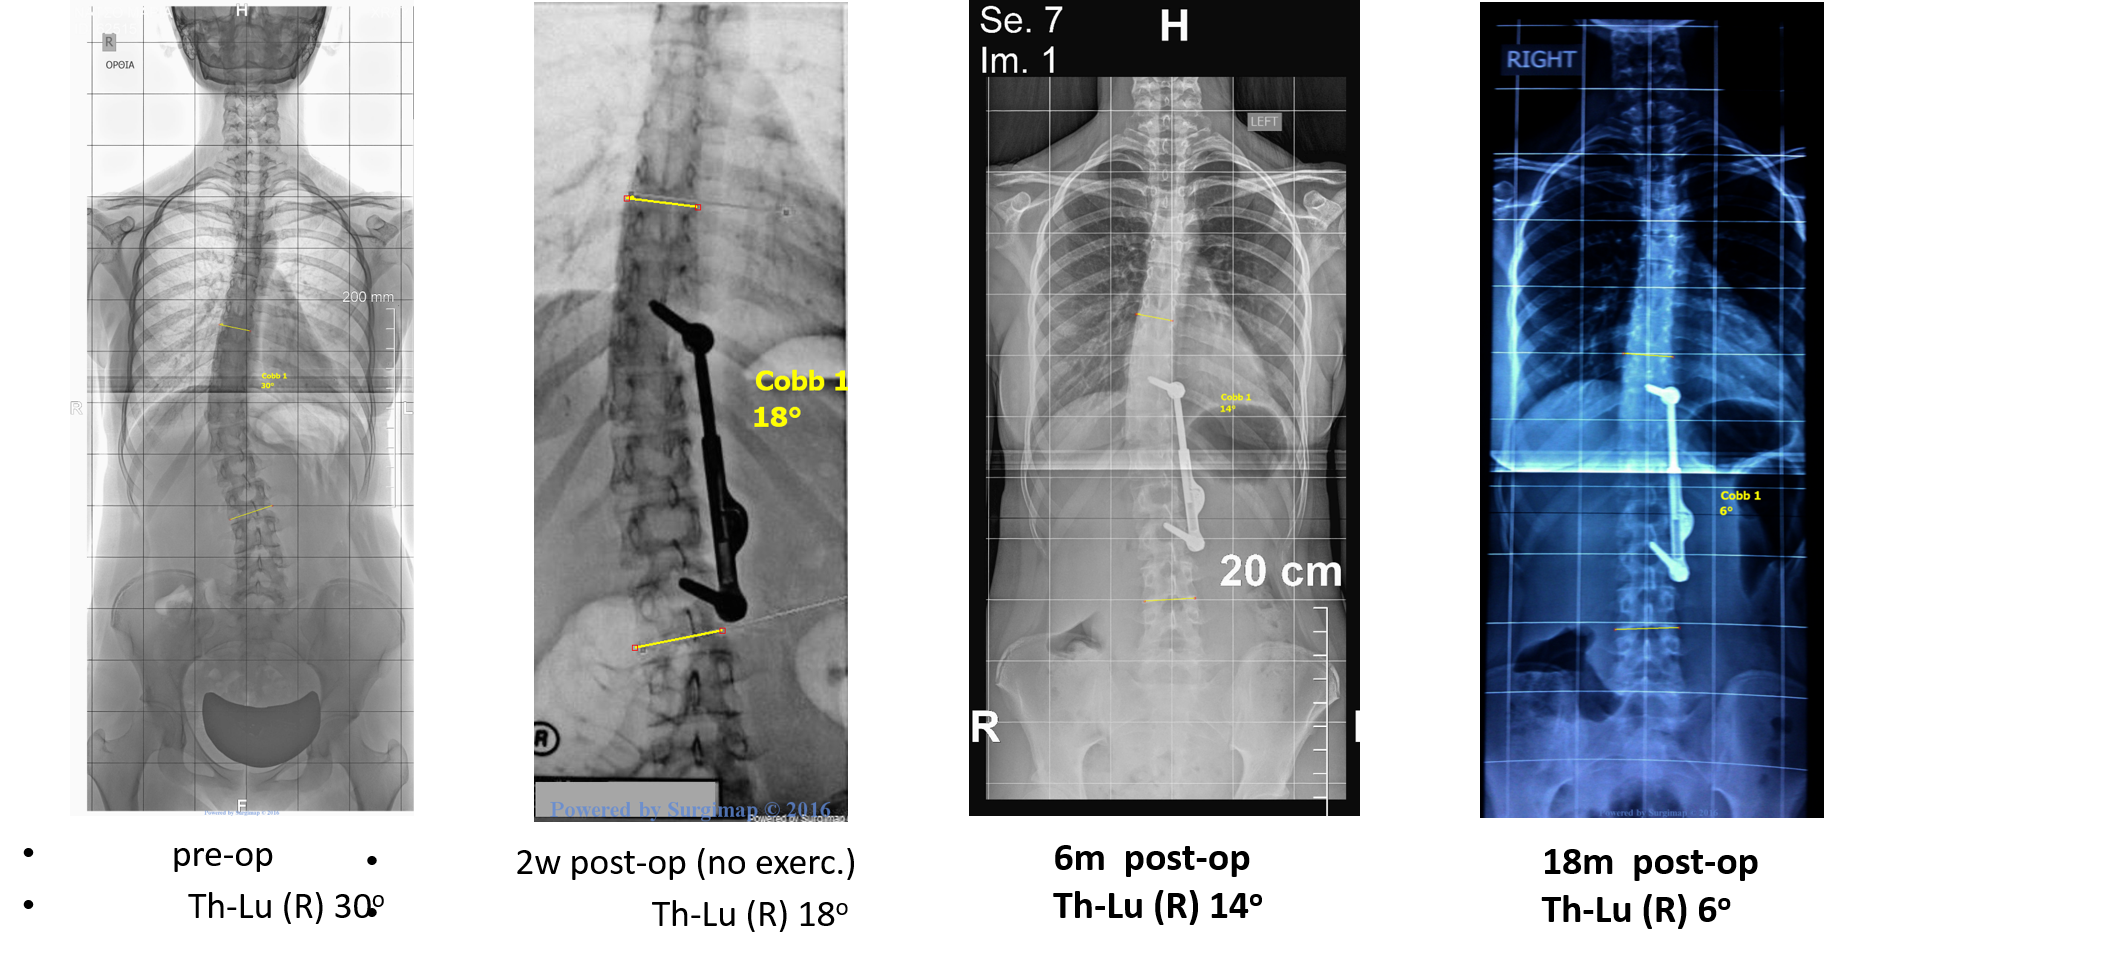

Τα αποτελέσματα της έρευνας έδειξαν πως ο μέσος όρος διόρθωσης της γωνίας Cobb, μετά την εφαρμογή του συστήματος ApiFix και των ασκήσεων με την μέθοδο Schroth, ήταν 40,1%. Η βοήθεια των ασκήσεων της μεθόδου Schroth φαίνεται να είναι καθοριστικής σημασίας, καθώς η ανάλυση πριν και μετά τις ασκήσεις, έδειξε βελτίωση περίπου 4,6 μοίρες ακόμα. Επίσης, οι ασκήσεις με την μέθοδο Schroth βελτίωσαν σημαντικά και την γωνία της στροφής της σκολίωσης (ATR) κατά 2,6 μοίρες, καθώς και τον πόνο και την εμφάνιση του ασθενούς, σύμφωνα με τα ειδικά ερωτηματολόγια που χρησιμοποιήθηκαν για τους σκοπούς της έρευνας. Οι ασθενείς με την μέθοδο Schroth έχουν μια εφ’όρου ζωής εκπαίδευση για την διατήρηση μιας διορθωμένης στάσης κατά τις καθημερινές τους δραστηριότητες, η οποία εξασφαλίζει την μακροπρόθεσμη σταθεροποίηση του θεραπευτικού αποτελέσματος.